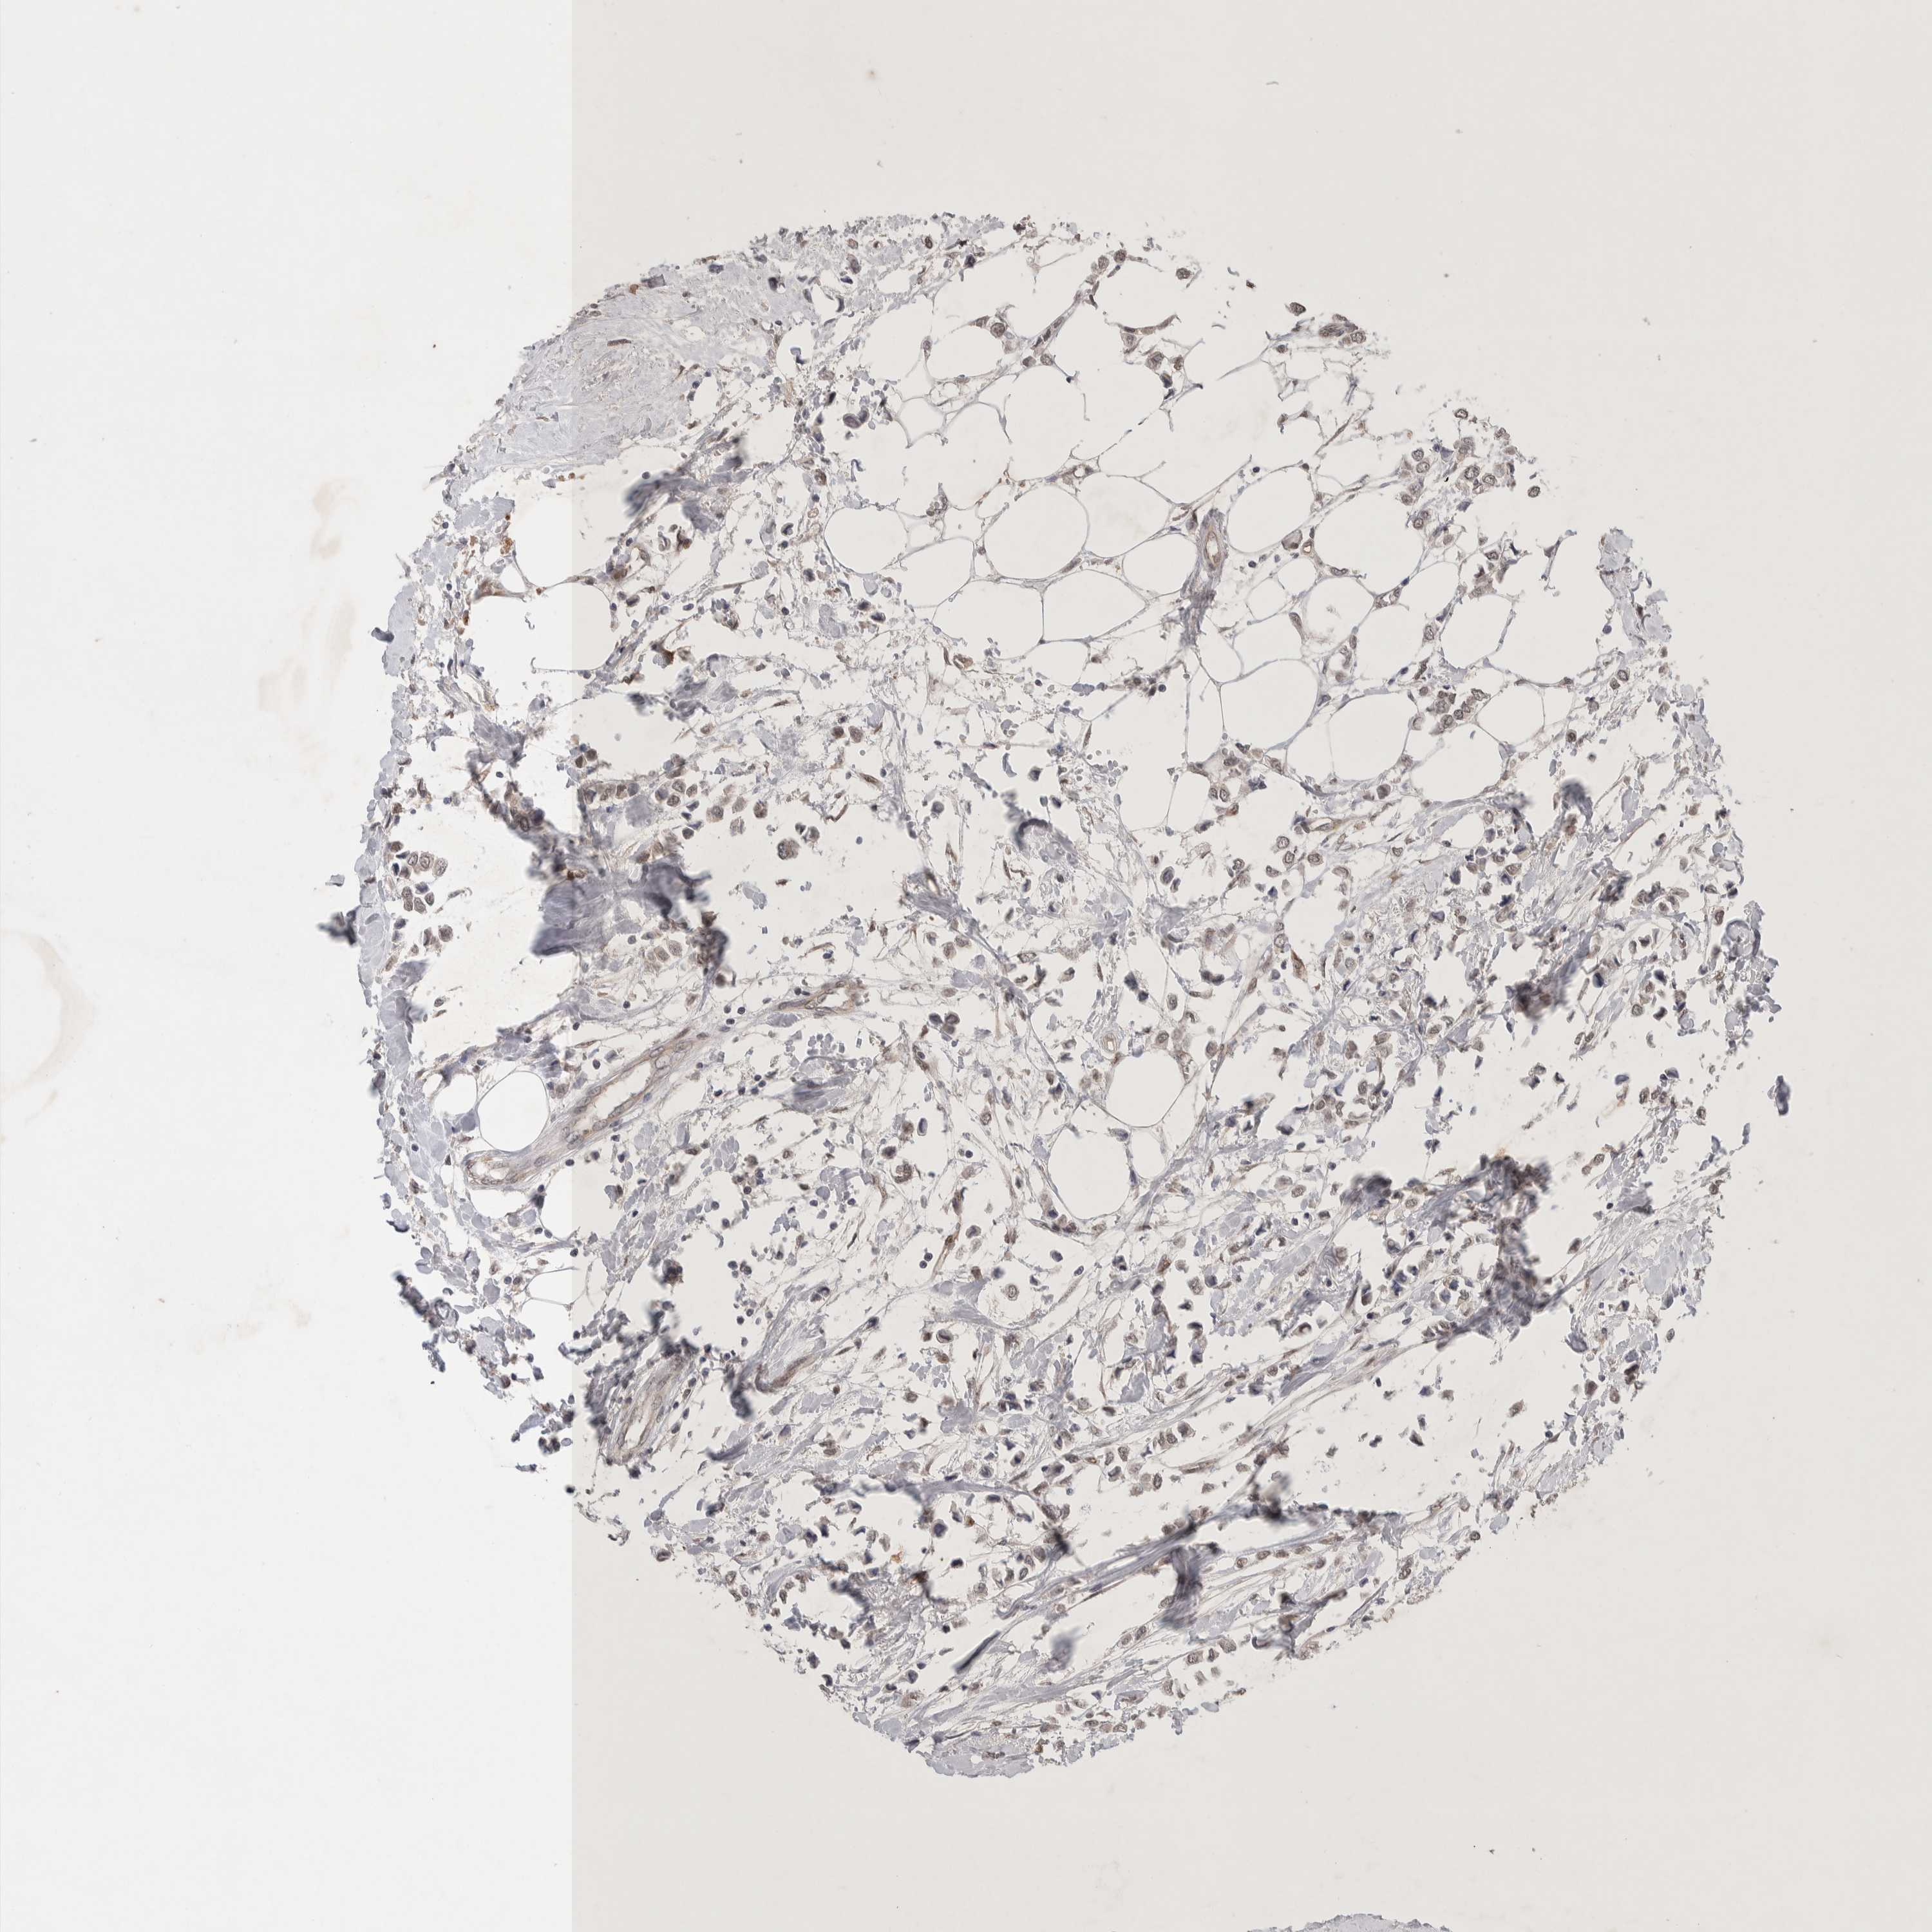

CANCER BREAST CANCER Show tissue menu

BRCA TCGA BRCA VALIDATION PROTEIN EXPRESSION